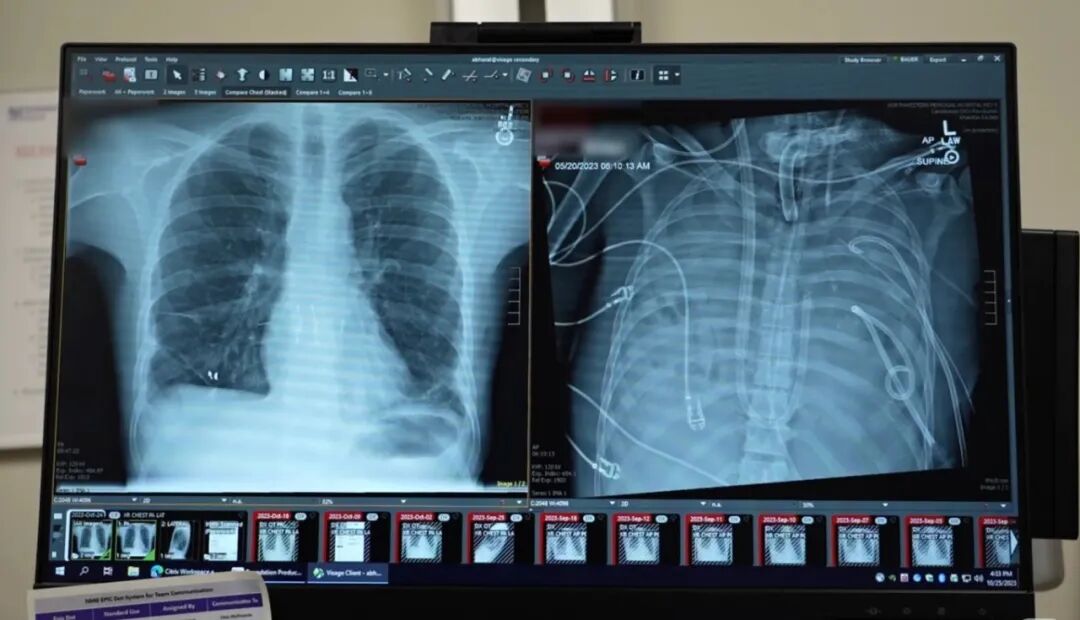

本次团队展示了一张图,是患者术后两年的胸片。两片新肺清晰干净,没有积液,没有实变。这个曾经过着等死的年轻人,现在自己来签了知情同意书,他还在康复之后亲自签署了同意公开病例的文书。